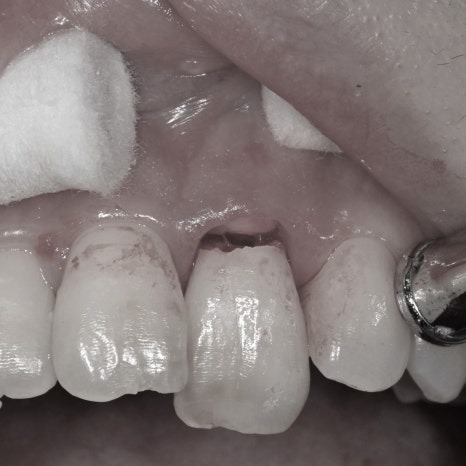

발치와 동시에 임플란트를 식립한 후 방사선사진

임플란트 수술이 잘 이루어지고 난 후에는

임플란트 치아를 만들기 위해

본 뜨는 작업(인상채득ㅇ)을 해야합니다.